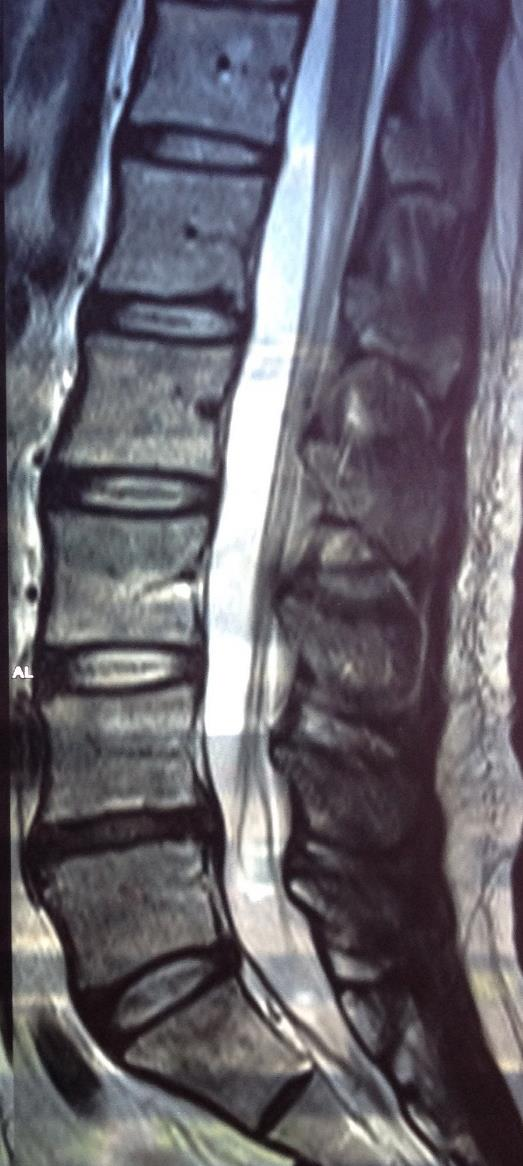

Slip Disc Recovery Time . A herniated disc tends to heal gradually and usually progresses through stages, each with its own characteristics and challenges. Herniated, or slipped, discs in the lower back (called the lumbar spine area) are relatively common, especially for people in middle age. Think you might have a slipped disc? Find out more about symptoms, risks and treatments. The disc often puts pressure on a nerve root which causes pain. While every individual is different, here is a general timeline for when to expect to get back to regular activity and exercise following. Advice to improve your movement, fitness, and overall health from the world's #1 in orthopedics. The good news is that in most cases — 90% of the time — pain caused by a herniated disc will go away on its own within six months. Clinically reviewed by leonel hunt, md, a herniated disc can disrupt your life, but healing. A slipped disc often causes sudden severe lower back pain. The average amount of time it takes for a herniated disk to heal is four to six weeks, but it can get better within a few days depending on how severe the herniation was.